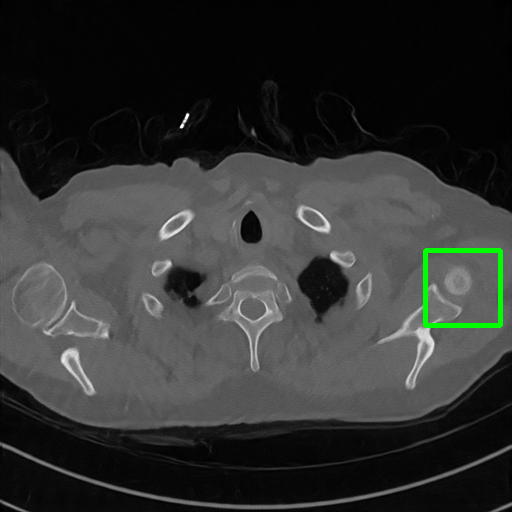

Generalizablity on COVID-19 dataset. Finally, we use slices of another patient in the COVID-19 dataset to test the generalizability of trained models, and quantitative performances are compared in Table 4. ImgTrans and DuDoTrans have achieved a larger improvement about 4-5 dB over CNN-based methods, which shows that the long-range dependency modeling ability helps capture the intrinsic global property of general CT images. Further, our DuDoTrans exceeds ImgTrans about 0.4 dB in all cases, even larger than the original NIH-AAPM dataset. The improvement ensures that DuDoTrans generalizes well to out-of-distribution CT images. Besides, we also show the visualization images in Fig. 5 when = 96. Coinciding with the quantitative comparison, our DuDoTrans show better reconstruction on both global patterns and local details.